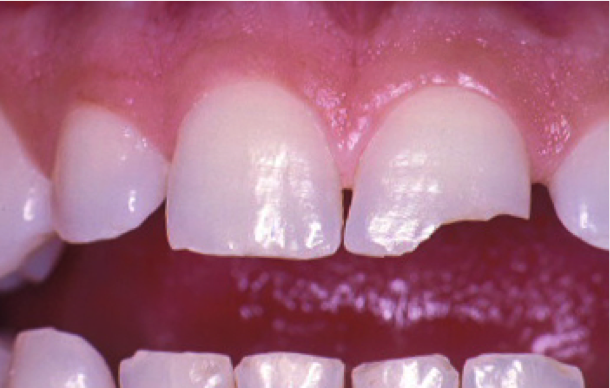

Polymerization Shrinkage Stress and the C-factor

Davidson’s research sheds light on polymerization shrinkage stress, specifically the configuration factor, or C-factor, which is the ratio of the restoration’s bonded to unbonded (free) surfaces of the tooth preparation.3 The higher the C-factor, the greater the potential for disruption of the bond due to polymerization shrinkage and shrinkage stresses of the composite, causing gaps that may be responsible for adverse events such as postoperative sensitivity or restoration failure. For example, in a Class IV restoration with one bonded and four unbonded surfaces, there is a C-factor of one, or 0.25, which is correlated with a low risk for adverse polymerization shrinkage effects (Figure 3). Conversely, there is a high risk of adverse polymerization shrinkage effects in more intricate cavity preparations such as Class I or Class V restorations with five bonded surfaces and only one unbonded (free) surface, for a C-factor of five (Figure 4 and Figure 5). The C-factor of two in routine Class II and Class III restorations with four bonded and two unbonded (free) surfaces is associated with a moderate risk for adverse polymerization shrinkage effects.

Fig 3. Image of a Class IV restoration with a C-factor of one has just one bonded surface and four unbonded surfaces. It has a low risk for adverse polymerization effects.

Figure 3